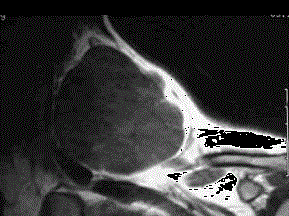

问题 37岁女性,左侧颈部肿块渐进性增大,无压痛,局部皮温不高,CT、MRI扫描如图所示,请选择正确的描述或诊断 ( )

选项 A、MRI的TWI呈高信号,其内可见分隔 B、考虑为淋巴管囊肿 C、增强扫描未见强化 D、MRI的TWI呈低信号 E、CT发现左侧颈后三角区可见低密度肿块影

答案 ABCDE